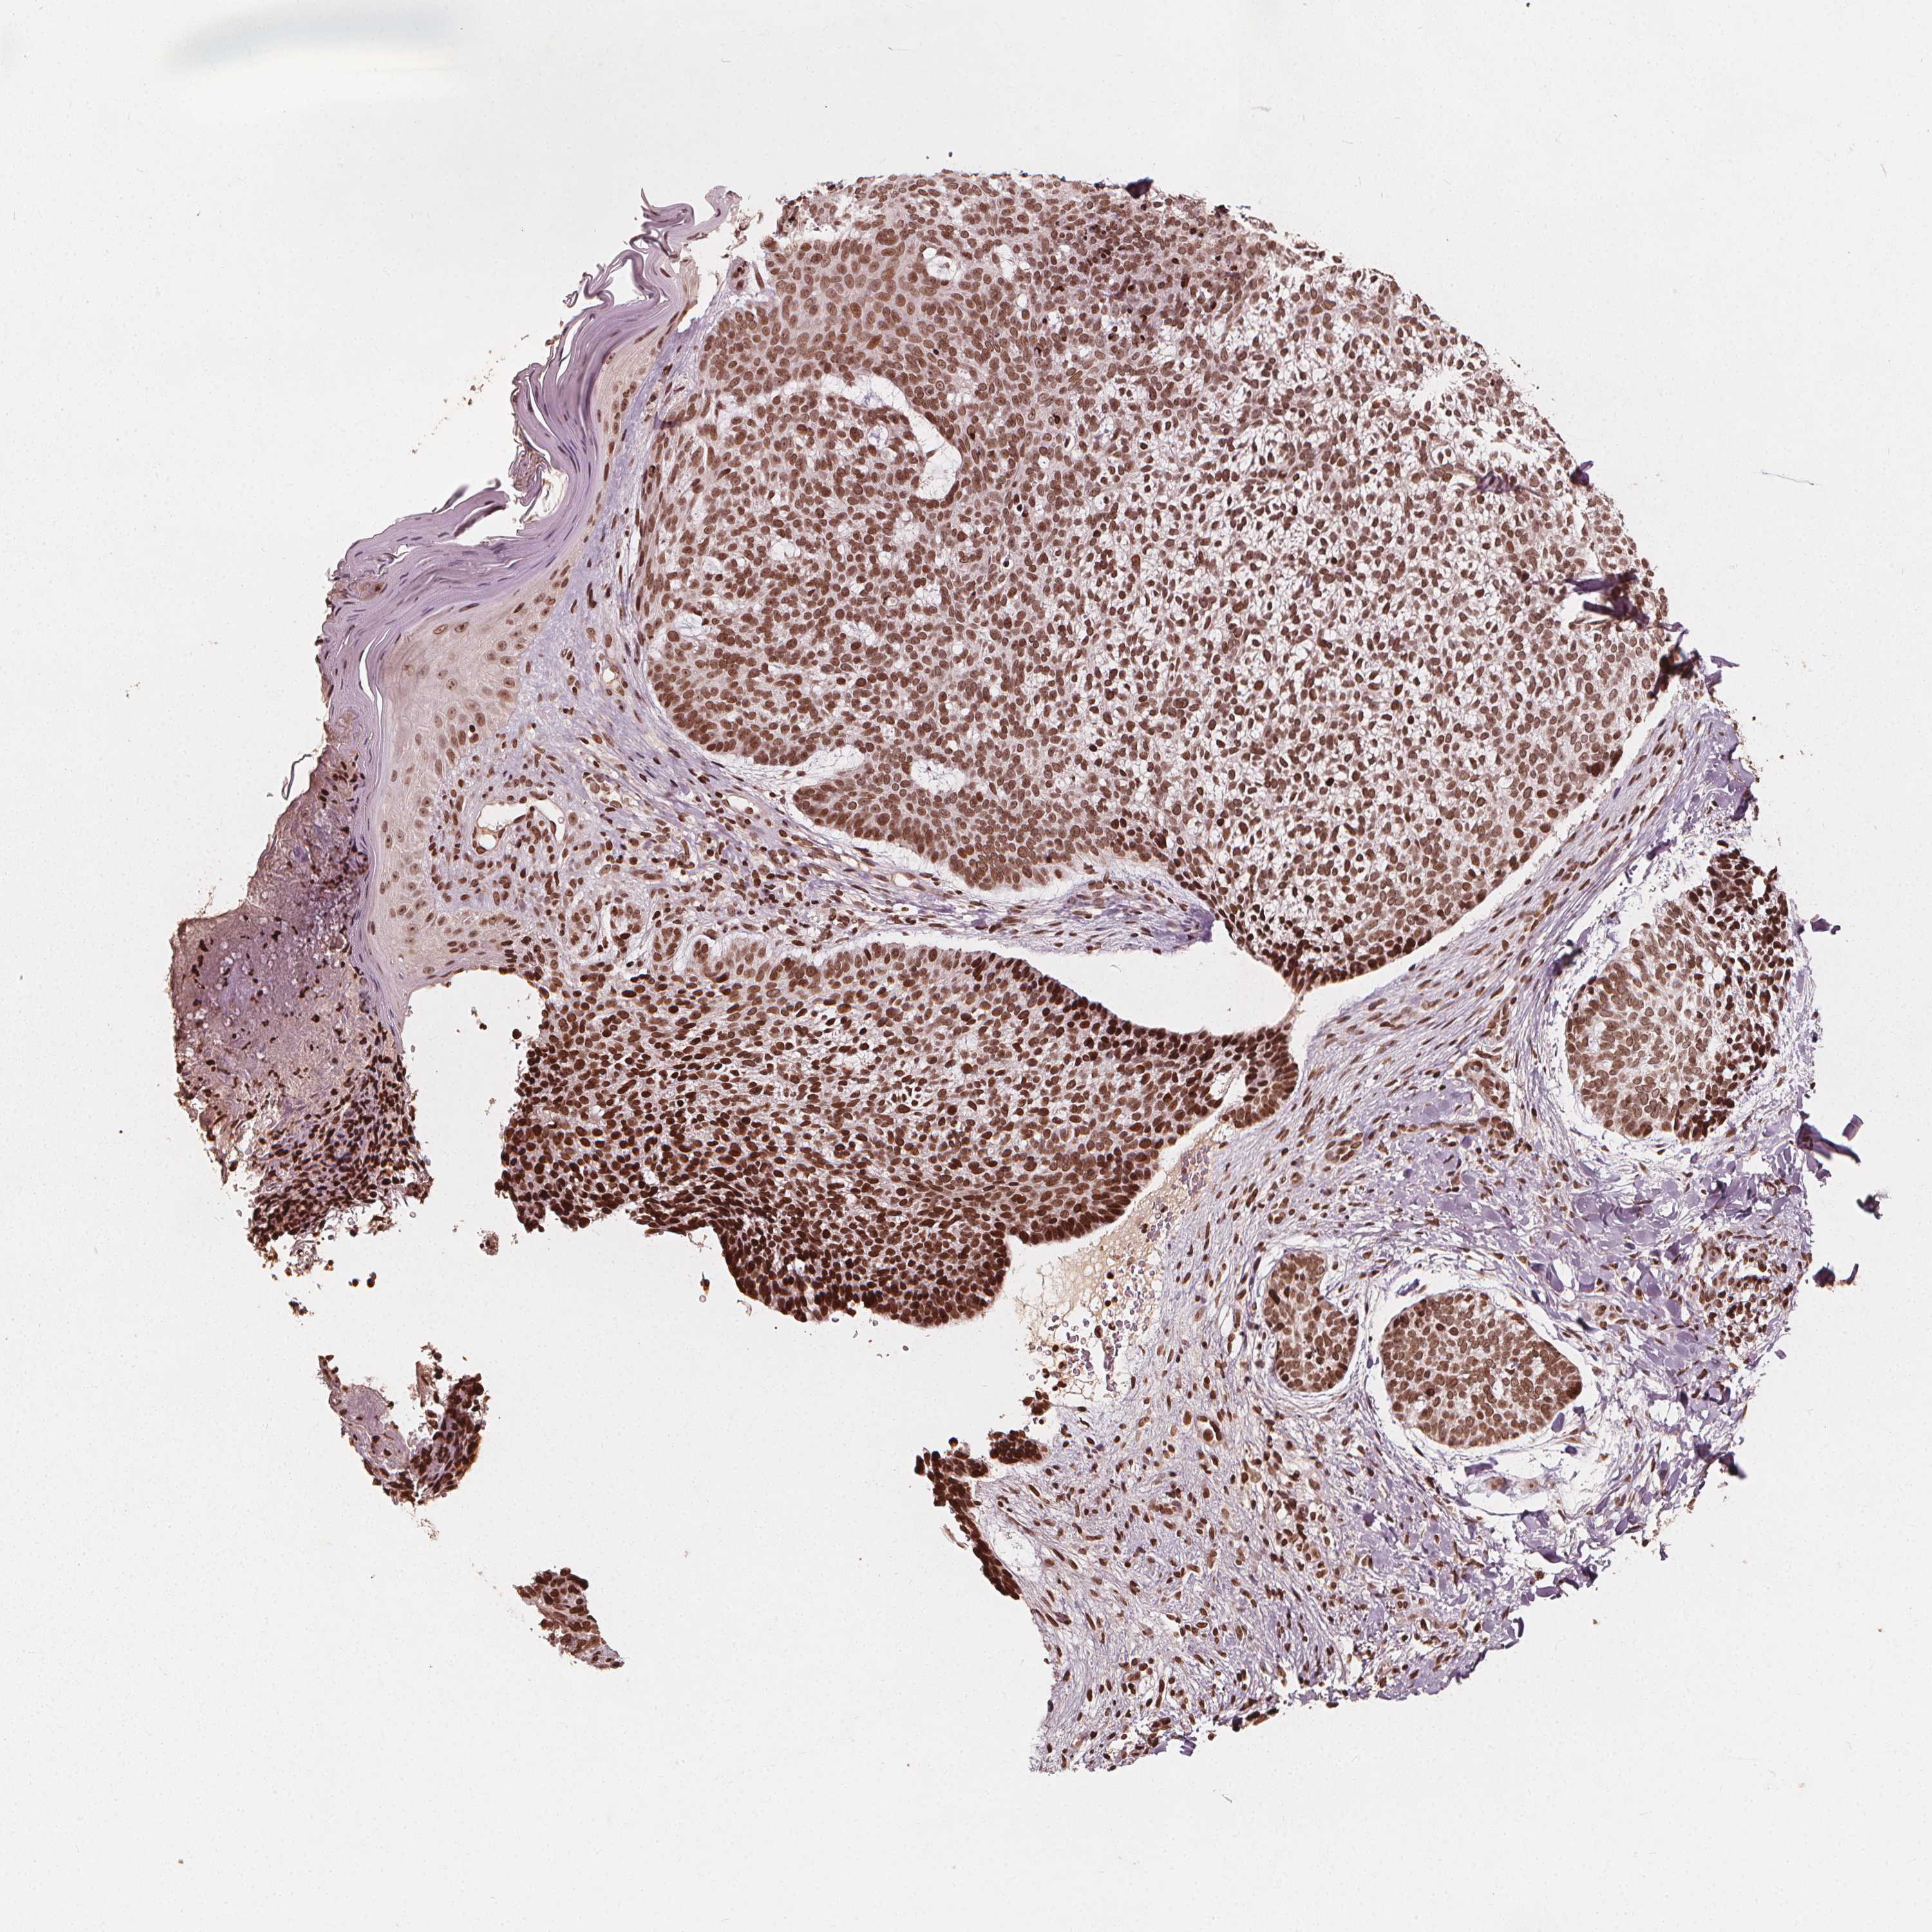

SKIN CANCER - Protein expressioni

A mouse-over function shows sample information and annotation data. Click on an image to view it in a full screen mode. Samples can be filtered based on level of antibody staining by selecting one or several of the following categories: high, medium, low and not detected. The assay and annotation is described here.

Each image is clickable and will lead to virtual microscopy that enables deeper exploration of all samples and also displays staining intensity scores, fraction scores and subcellular localization as well as patient and tissue information for each sample.

Antibody HPA042570

Basal cell carcinoma